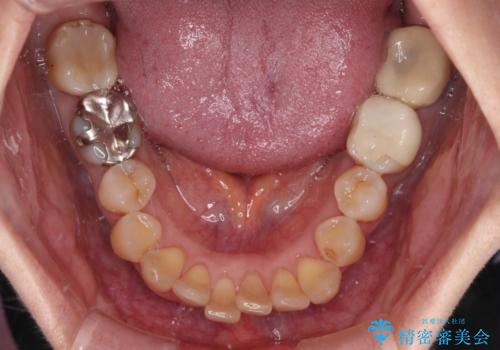

- 上下前歯のデコボコと、奥歯の銀歯を気にして来院された患者様です。

概ね歯列が整ったところで銀歯の全てをセラミッククラウンなどに置き換え、その後インビザラインを1セット使用して仕上げていくこととしました。

矯正治療の後半にはホワイトニングもされ、スッキリした口元に仕上げることができました。